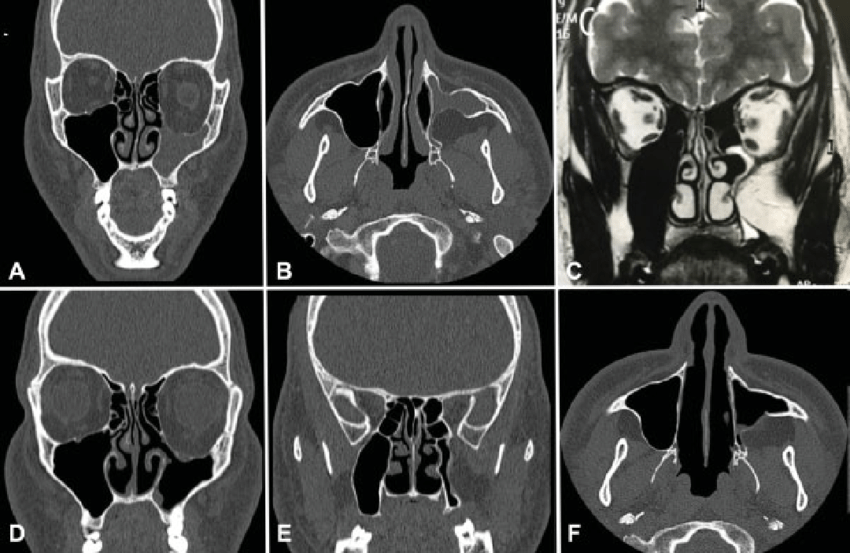

Silence sinus syndrome refers to the consequences of asymptomatic chronic maxillary sinusitis. Collapse of the orbital floor can lead to enophthalmos or hypoglobus. One of the major risk factor is anomalies of nasal structure. Management involves surgery. Reference: https://eyewiki.aao.org/Silent_Sinus_Syndrome#Management Image via: https://www.researchgate.net/publication/339542645_Reversible_Endoscopic_Medial_Maxillectomy_Endonasal_Approach_to_Diseases_of_the_Maxillary_Sinus/figures?lo=1&utm_source=google&utm_medium=organic